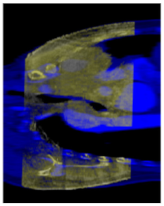

The fundamentals of CBCT imaging are the same as the CT; the difference between them is the sampling process during a scan. The CBCT is a special X-ray-based imaging technology. By a dedicatedly designed X-ray generator, the X-ray irradiation in a pyramidalis volume is mainly designed for dental imaging or for reducing the radiation damage in head scan, and the exposure dose is lower than the annular CT device [,,]. For the migrated CBCT which is applied to a body scan, the scan device only moves along the single direction of the z-axis without the rotation around the patient, so it is impossible to reconstruct an image with the same level of quality as the annular CT imaging. As Figure 9 shows, in some CBCT body scans, there are some areas where the data are obviously missing. An image of this quality is insufficient for diagnosis, but medical experts still use the advantage of a low exposure dose of the CBCT scan by image guide technology.

Figure 9.

(a,b) are the superposition of the CT and the CBCT sequences, the yellow dashed circle indicates the region with an abundant projection signal, and the rectangular boxes indicate two examples of missing data areas in the CBCT scan.

Considering that the fundamentals of CBCT and CT are the same, a pixel in a CBCT image has the same meaning as in the CT, even though the CT has accumulated added signal by more sampling angles; however, the value of the reconstructed image needs to be normalized in 0 to 255, the same as the range of a CBCT image. Therefore, for the area with better image quality in the CBCT sequence, the content is very similar to the CT image.